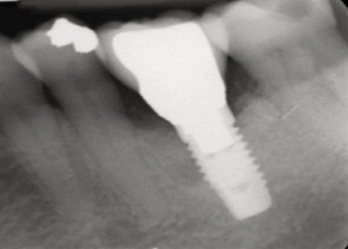

Fig 17. Radiograph showed symmetrical infrabony defect affecting 50% of the implant surface.

Figure 17

Clinical examination showed 2 mm of buccal recession with a shallow vestibule and absence of keratinized attached gingiva against the crown with 8 mm of circumferential pocketing accompanied by bleeding upon probing (Figure 15 and Figure 16). A periapical radiograph showed a symmetrical vertical osseous defect causing the loss of 50% of the bone around the implant (Figure 17). Because the patient had made a significant investment of time and finances to replace her lost tooth with the implant, she desired that the implant and restoration be retained, if feasible.